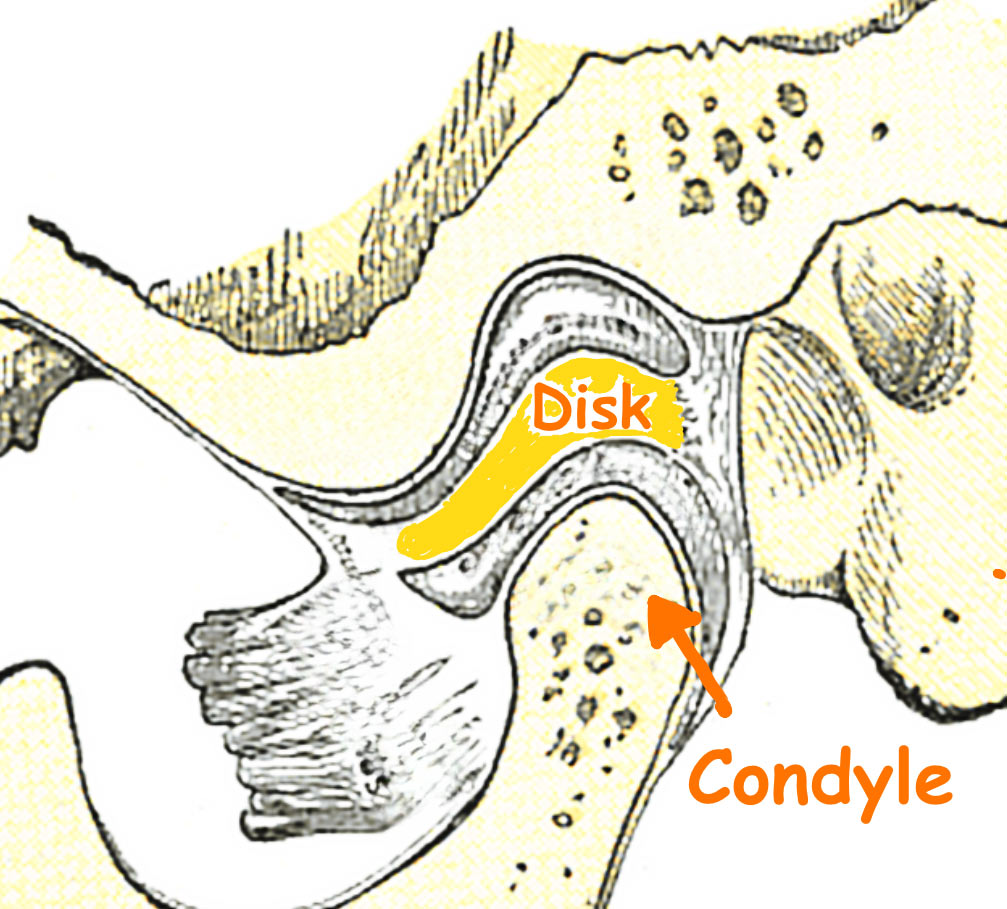

Understanding the TMJ:

TMJ stands for temporomandibular joint and is the hinge joint that connects the jawbone to the skull. The TMJ consists of bones, muscles, ligaments, and a small disc that cushions the joint to allow smooth jaw movement. Located on each side of the head in front of the ears, the pair of TMJ joints function in synchronized harmony allowing for smooth movements of the lower jaw.

The TMJ joint uniqueness:

- The TMJ combines both a hinge and a sliding motion, making it one of the most complex joints in the body.

- The jaw moving apparatus consists of twin joints with one TMJ present on each side of the lower jaw.

- TMJ joints must function in orchestrated unison to achieve smooth jaw movement.